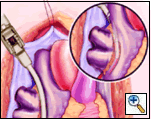

Holding the closed Medtronic bipolar irrigated radiofrequency clamp in the surgeon’s left hand, the malleable clamp tips are gently curved outward. The lower jaw of the open bipolar clamp is placed into the open end of the Red Robinson catheter and the catheter gently withdrawn until the end is visible under the IVC. The catheter is removed and the clamp closed on the atrial side of the pulmonary vein/left atrial interface. Energy is applied until a transmural ablation is assured.